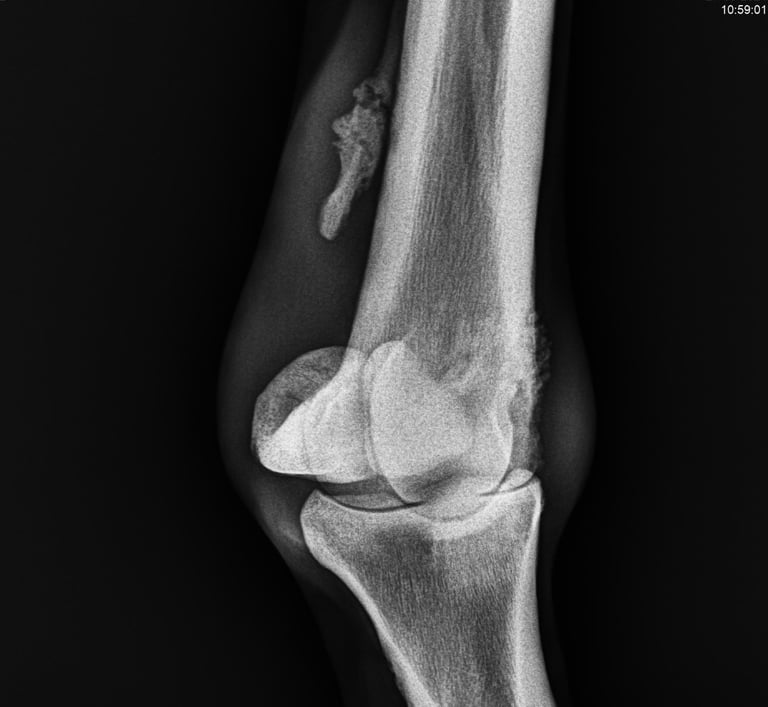

DIAGNOSTICO POR IMAGENES: ECOGRAFIA Y RADIOGRAFIA